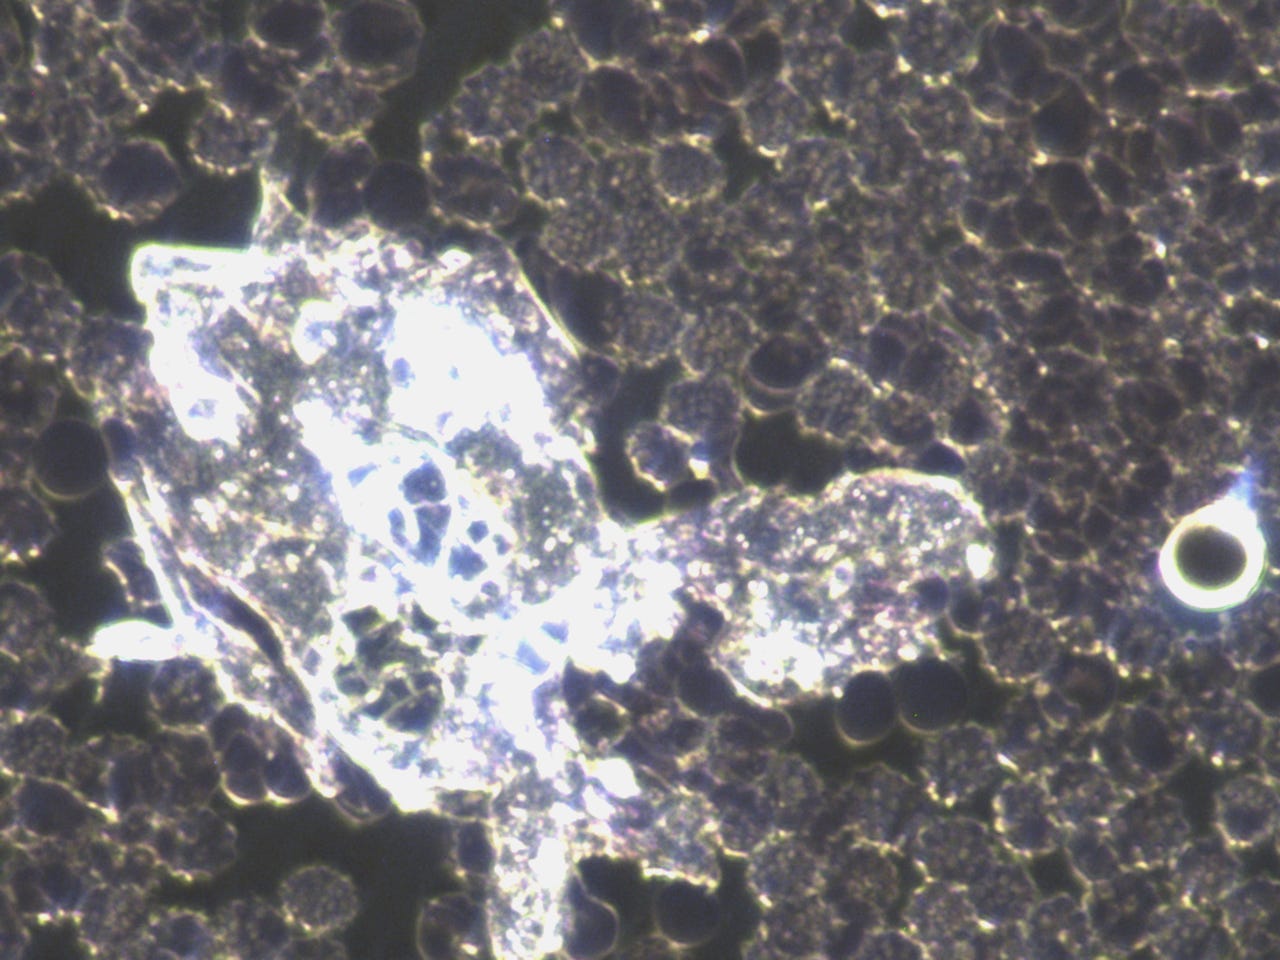

subscribed. Thank you so much. He asked to see my blood before the frequency treatments. The photo’s posted in the previous posts, especially the ones that showed the quantum dots in my blood after the MAH (Major Auto Hemotherapy) with ozone was before the frequency treatments. I am posting them here again, however, I will post some prior to that also.Quantum dots in my blood from Heparin pharmaceutical:

This was the morning after all the quantum dots destroyed my blood:

Anyway here are more before pictures;

I think these really show how messed up my blood was prior to the frequency treatments. I will always be grateful to